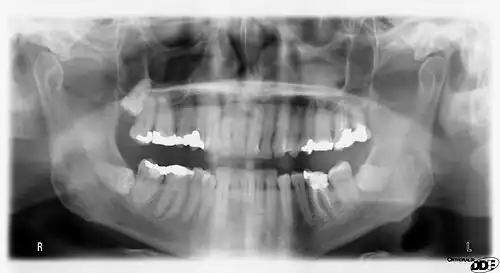

A panoramic radiograph is a panoramic scanning dental X-ray of the upper and lower jaw. It shows a two-dimensional view of a half-circle from ear to ear. Panoramic radiography is a form of focal plane tomography; thus, images of multiple planes are taken to make up the composite panoramic image, where the maxilla and mandible are in the focal trough and the structures that are superficial and deep to the trough are blurred.

Orthopantomograms (OPTs) are used by health care professionals to provide information on:

- Impacted wisdom teeth diagnosis and treatment planning - the most common use is to determine the status of wisdom teeth and trauma to the jaws.

- Periodontal bone loss and periapical involvement.

- Finding the source of dental pain, and when carrying out tooth-by-tooth diagnosis.

- Assessment for the placement of dental implants

- Orthodontic assessment. pre and post operative

- Diagnosis of developmental anomalies such as cherubism, cleido cranial dysplasia

- Carcinoma in relation to the jaws

- Temporomandibular joint dysfunctions and ankylosis.

- Diagnosis of osteosarcoma, ameloblastoma, renal osteodystrophy affecting jaws and hypophosphatemia.

- Diagnosis, and pre- and post-surgical assessment of oral and maxillofacial trauma, e.g. dentoalveolar fractures and mandibular fractures.

- Salivary stones (Sialolithiasis).

- Other diagnostic and treatment applications.[2]